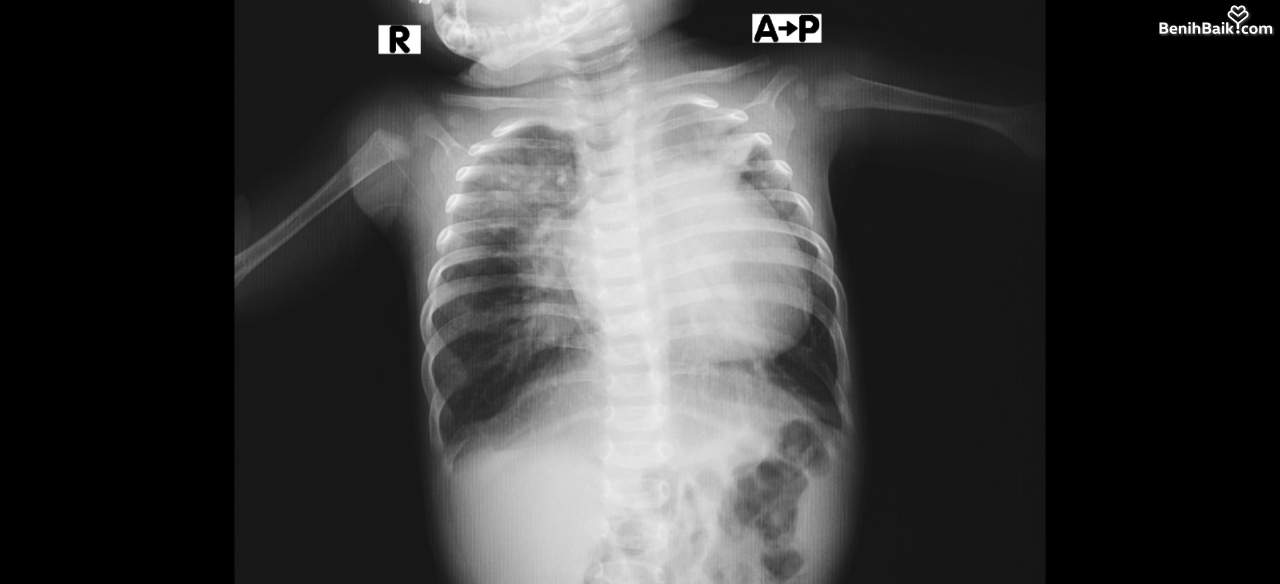

Usianya baru 8 bulan, tapi Audriella harus menanggung penyakit mematikan! Jantungnya bocor dan paru-parunya infeksi. Penyakit itu tak hanya merenggut ketenangan dan senyum mungilnya, tapi menoreh luka di hati orang tuanya.

Kondisi Audriella saat ini menunjukkan banyak perkembangan. Saat kontrol pada 16 Oktober lalu, paru-parunya dinyatakan sudah sembuh oleh dokter. Namun, ada kabar kurang baik, kebocoran pada jantungnya semakin membesar. Dari ukuran 4 mm kini menjadi 1 cm, dan dokter telah menjadwalkan operasi pada Januari 2026.

Puji syukur, kondisi paru-parunya menunjukkan perkembangan yang baik. Namun, untuk jantungnya masih harus ditangani dengan obat-obatan sambil menunggu paru-paru Audriella benar-benar pulih.Kami, orang tua Audriella, ingin mengucapkan terima kasih yang sebesar-besarnya kepada #TemanBaik yang telah peduli dan membantu kami, terutama untuk kesembuhan anak kami tercinta.